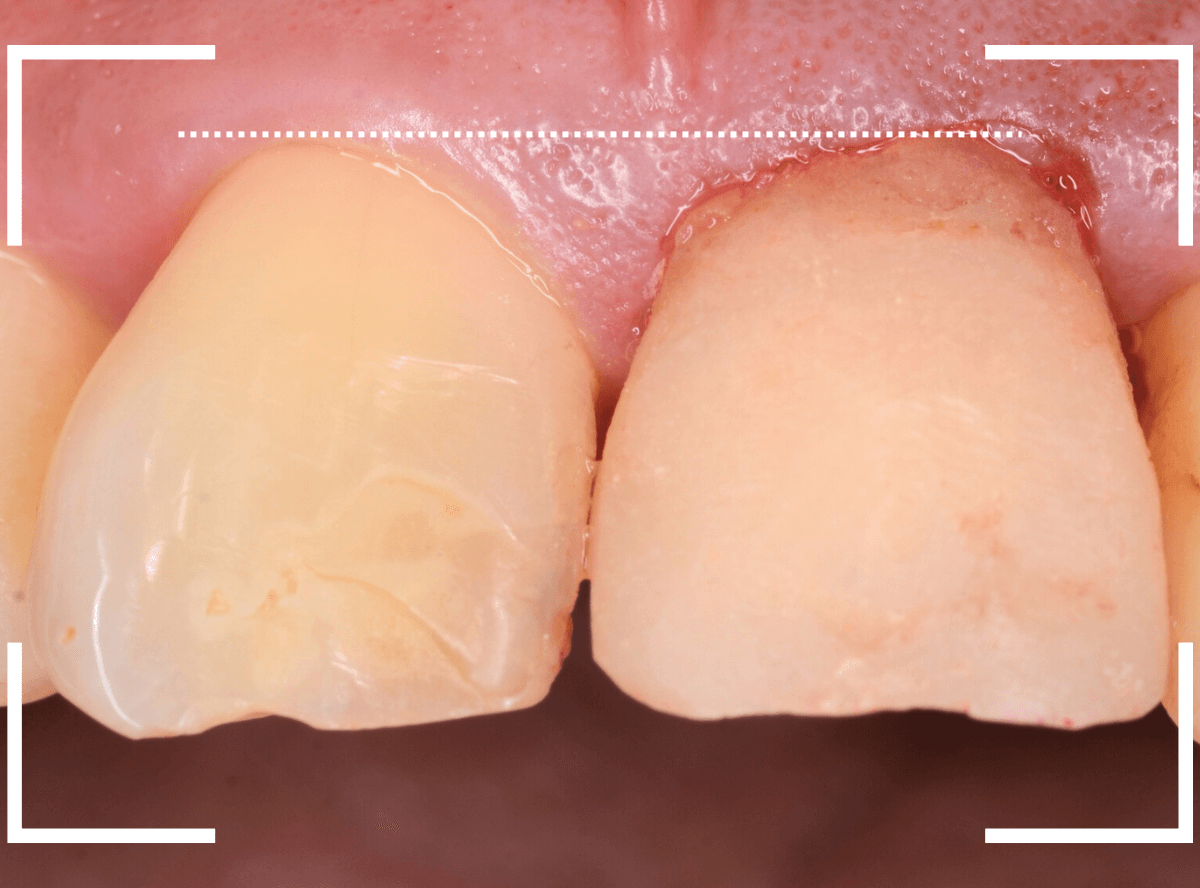

しばらく経過観察して、歯肉が落ち着いたところです。

さし歯を入れるのに心配ない程度の歯の高さが確保でき、さし歯を作るための準備が整いました。

今回は、審美性と、清掃性が高く、歯周病が進行しにくいという利点を考慮して、ジルコニア・セラミックでの治療を選択されました。

ジルコニア・セラミックset後の状態です。

仮歯で細かく調整したおかげで、下の歯のかみ合わせは若干の調整で済む事ができました。